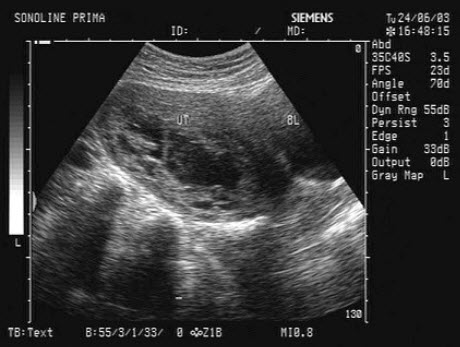

如图,初步超声诊断为()

A.二尖瓣返流

B.三尖瓣返流

C.主动脉瓣返流

D.肺动脉瓣返流

E.以上均不是